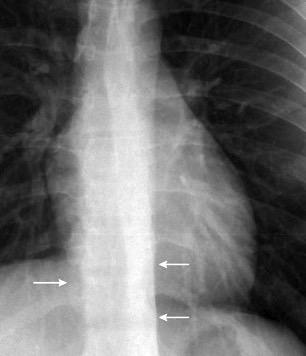

62. LÍNEAS PARAESPINALES. DESPLAZAMIENTO BILATERAL DE

64. LÍNEA PARAESPINAL. DESPLAZAMIENTO UNILATERAL DE